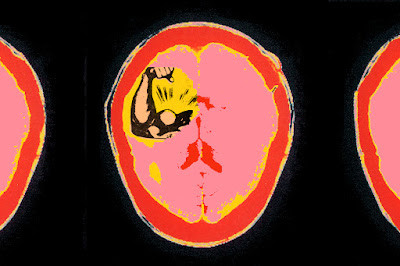

For the July/August issue of The Atlantic: having power, being in charge, can have the same effects as a traumatic brain injury; causing the person to act "more impulsive, less risk-aware, and, crucially, less adept at seeing things from other people's point of view."